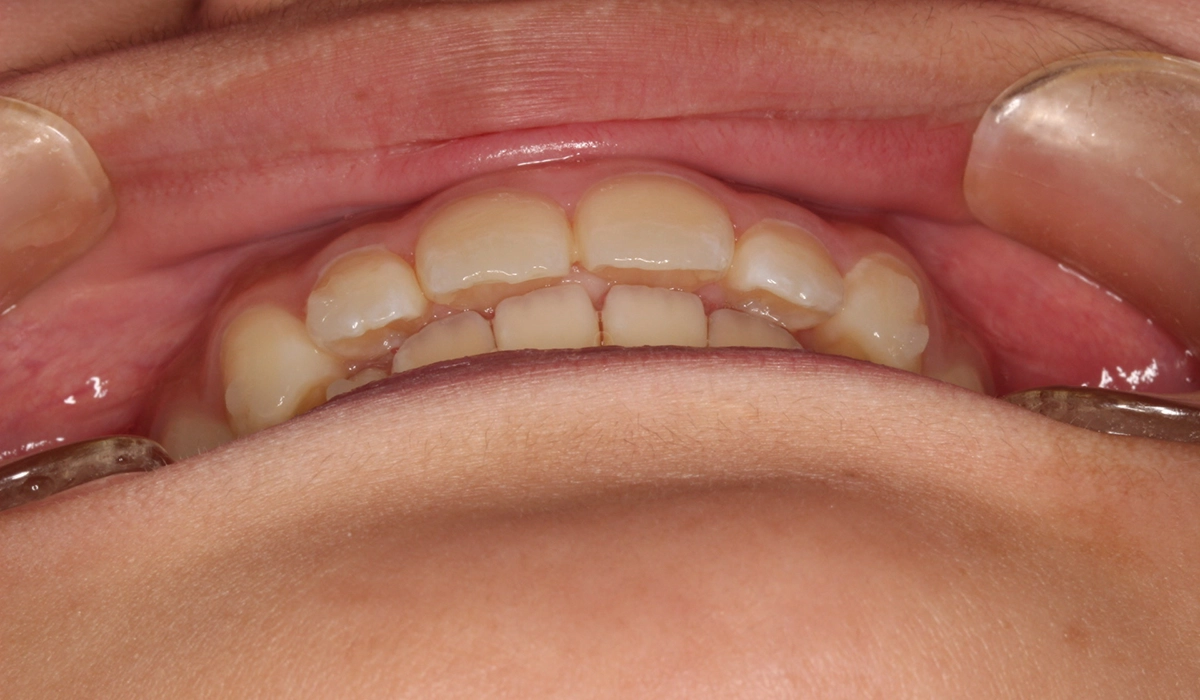

術前:前歯部

術後:前歯部